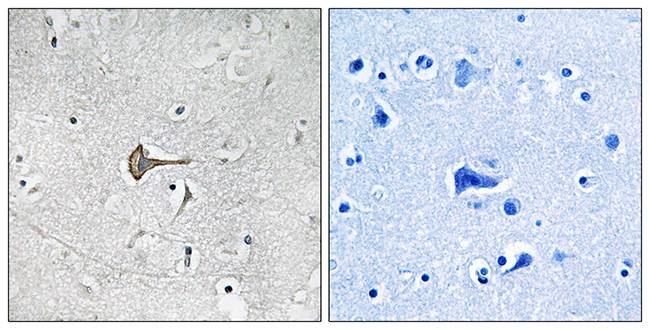

Anti-KCNQ3 AntibodyA96982

ApplicationsELISA, ImmunoHistoChemistry

ReactivityHuman, Mouse, Rat

Product group Antibodies

Anti-KCND2 AntibodyA96983

ApplicationsELISA, ImmunoHistoChemistry

ReactivityHuman, Mouse, Rat